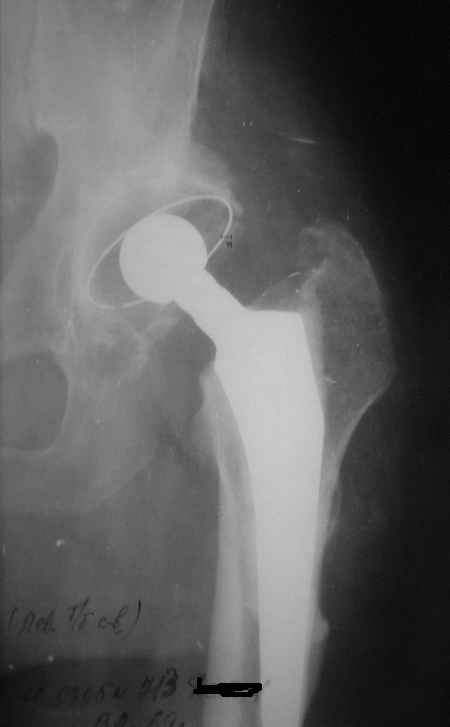

Уважаемые коллеги,Мужчина, 69 лет, в декабре 2004 г перенес тотальную цементную артропластику . Через 3 мес после операции на фоне прогрессирующих болей в средней и проксимальной третях бедра при нагрузке возникли резкие боли и появилось опухолевидное болезненно образование. Процесс сопровождался резким одномоментным укорочением ноги.

В феврале 2005 г. выполнена ревизионная артропластика, завершившаяся прогрессировавшим в течение 1-2 мес укорочением ноги. В настоящее время ходит только с костылями, при движениях в тазобедренном суставе испытывает резкие боли, ощущает хруст. Попытка осевой нагрузки бедра сопровождается ощущением "перемещения поршня" и заметным по внешним ориентирам укорочением левой ноги на 1-1,5 см.

Наверное перфорация стенки при первичном протезировании и неадекватный размер Вагнера при ревизионном? Что-нибудь еще?

Я полностью поддерживаю Ваше мнение об интраоперационной перфорации при первичном протезировании, т.к. при внимательном рассмотрении рентгенограммы после этого этапа виден дефект кортикального слоя именно по задне-наружной поверхности .

И ножка Вагнера подобра плохо, и насчет возможной инфекции Вы совершенно правы, т.к. рана после второй операции заживала вторичным натяжением.

К сожалению, Р-граммы не захватывают полностью бедро, поэтому окончательное решение может быть после полноценного р-ского обследования. Однако думаю, что оптимальное решение - полнопокрытая ножка длинной не менее 200 мм, без привязки к типу протеза. Это может быть модульная система ZMR, Solution и др., главное - принцип. В отношении чашки тоже есть определенные сомнения. Думаю, что наш ин-т (РосНИИТО, СПб) смог бы сделать эту операцию.

Ситуация достаточно несложная. Основной массив бедренной кости сохранён. Лучше поменять чашку сразу, потому что ей не долго осталось жить. Слишком латерально поставлена. Предпочитаю RM чашки при ревизии. Ножка предпочтительней Solution. Если есть проблемы по замене, могу взять к себе без проблем.